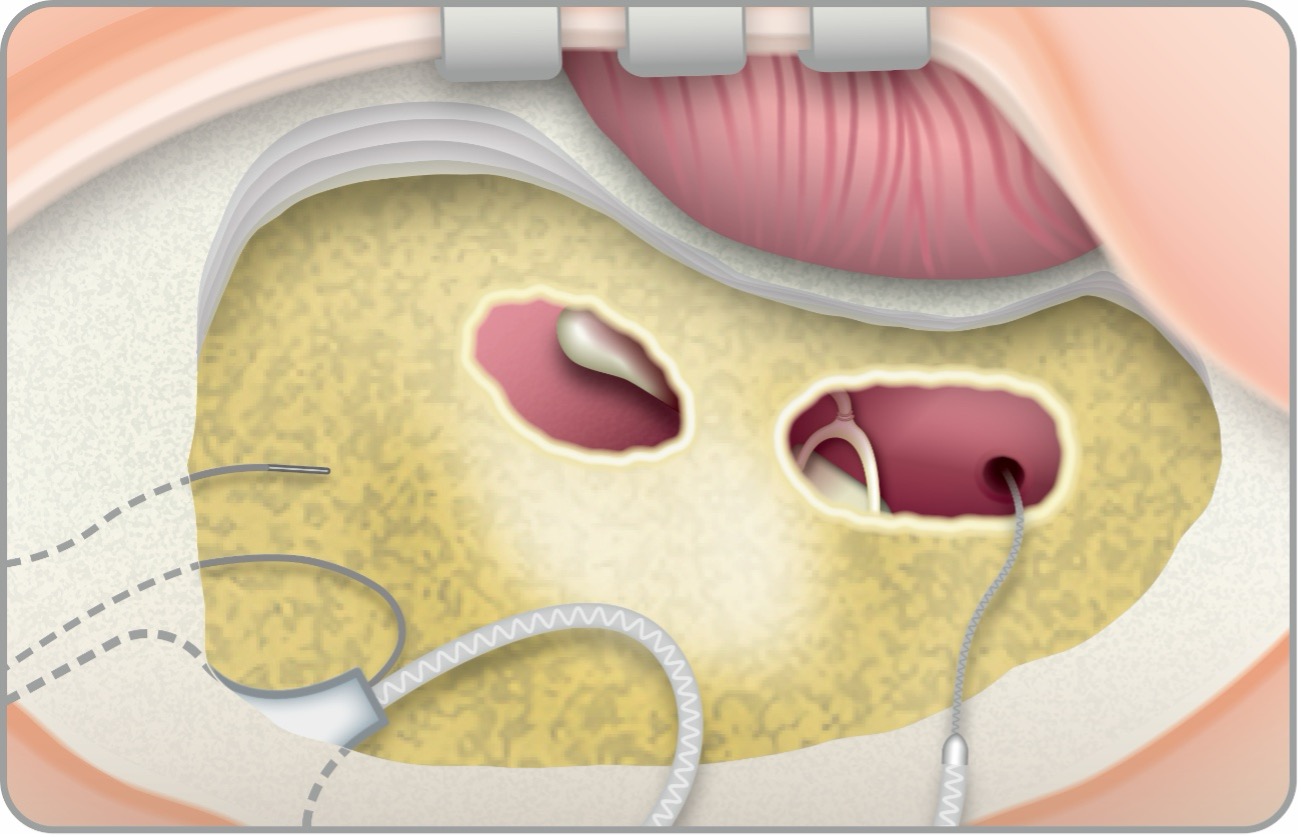

手術方法は、①耳後部の皮膚切開、②乳突削開:乳突洞および乳突蜂巣(Mastoid)の骨削開、③後鼓室開放、④人工内耳電極挿入の順に行います。②以降は通常、顕微鏡や手術用ドリルなどを使用して行われます。

人工内耳手術では、電極の挿入・作動と聴神経応答を客観的に確認するために術中モニタリングを行います。電極インピーダンスは各電極の電気抵抗を測定し、断線(オープン)や短絡(ショート)の有無、組織との接触状態を評価します。電気誘発複合活動電位(ECAP)は電極から刺激を与え、聴神経の複合活動電位を自動記録し、電極‐神経間の結合の確かさや術後マッピングの初期目安を得ます。単純X線/コンピュータ断層撮影(XP/CT)は電極配列の到達範囲・位置ずれ・巻き込みを画像的に確認し、異常所見があれば直ちに対応します。なお、電極インピーダンスが正常でも完全挿入や最適位置を保証するものではありません。ECAPは取得不能でも術後聴取が必ず不良とは限りません。画像では低被ばくのXPで全体像、必要時に高解像CTで細部を評価し、奇形例などでは術中透視(Cアーム)を限定的に用います。これらを組み合わせることで、安全性を高め、術後の聴取成績のばらつきを減らすことが期待できます。総じて電極インピーダンスECAP・XP/CTは「電極の健全性×神経反応×位置」の三点確認で、手術の質保証を支えます。